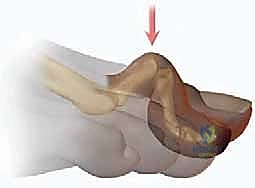

يحدث تشوه إصبع القدم المطرقية عندما يحدث خلل في التوازن بين العضلات والأوتار التي تتحكم في حركة هذه المفاصل. العضلات الباسطة (التي ترفع الإصبع لأعلى) والعضلات القابضة (التي تثني الإصبع لأسفل) يجب أن تعمل بتناغم مثالي. عندما تتغلب قوة العضلات القابضة، أو عندما تضعف الأربطة الداعمة، ينثني المفصل الأوسط (PIP) بشكل دائم.

أ. استئصال المفصل (Arthroplasty - Joint Resection)

في هذا الإجراء المتقدم، يقوم الدكتور هطيف بإزالة جزء صغير جداً من العظم عند المفصل المصاب (تحديداً رأس السلامية الدانية). إزالة هذا الجزء العظمي تخفف الشد الميكانيكي وتسمح للإصبع بالاستقامة.

* الميزة: يحافظ هذا الإجراء على بعض الحركة في المفصل، مما يجعله خياراً ممتازاً للمرضى الأصغر سناً أو النشطين.

* يتم استخدام أسلاك معدنية دقيقة (K-wires) لتثبيت الإصبع في وضع مستقيم أثناء التئام الأنسجة المحيطة بالعظم المقطوع.

ب. تثبيت المفصل (Arthrodesis - Joint Fusion)

يُعتبر هذا الإجراء المعيار الذهبي لحالات إصبع القدم المطرقية الصلب جداً والمؤلم، أو الحالات المرتجعة. يقوم الدكتور هطيف بإزالة الغضروف التالف من نهايتي العظمتين المكونتين للمفصل الأوسط (PIP)، ثم يتم دمج العظمتين معاً لتكوين عظمة واحدة صلبة ومستقيمة.

* الميزة: يوفر استقامة دائمة وقوية للإصبع، ويقضي على الألم تماماً لأنه يمنع أي حركة في المفصل التالف.

* طرق التثبيت: تقليدياً، تُستخدم أسلاك كيرشنر (K-wires) التي تبرز من طرف الإصبع وتُزال بعد عدة أسابيع. ولكن، مع التقدم التكنولوجي، يستخدم الدكتور هطيف في كثير من الأحيان غرسات داخلية حديثة (Intramedullary Implants) أو براغي دقيقة جداً تبقى داخل العظم، مما يجنب المريض إزعاج الأسلاك الخارجية ويسرع من عملية التأهيل.